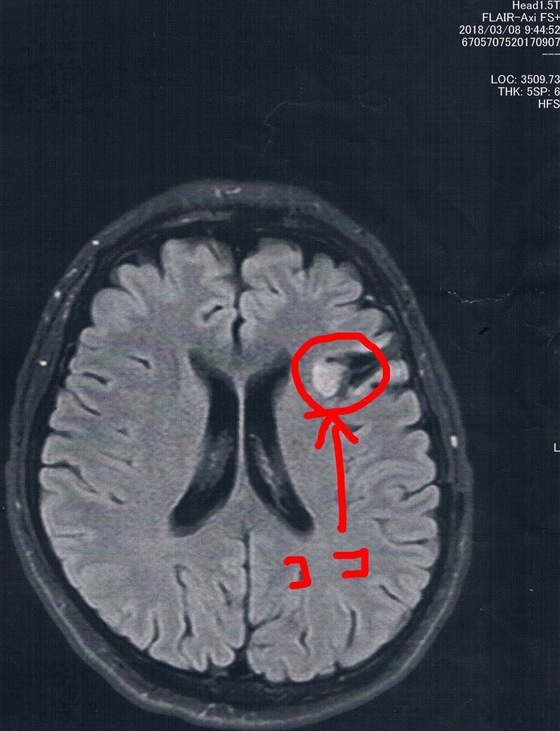

前回2018/3/8(手術後44ヶ月)のMRI画像

MRI検査の結果、半年前と比べても変化は無いように見えるが、

一年前やそれ以前の画像と比べると若干変化があるようにも見える。

と先生が言う。

半年毎の検査ではMRI画像上は変化が無いように見えてたけど、年単位の時間ではちょっとづつ増えているんだろうなぁ。。。